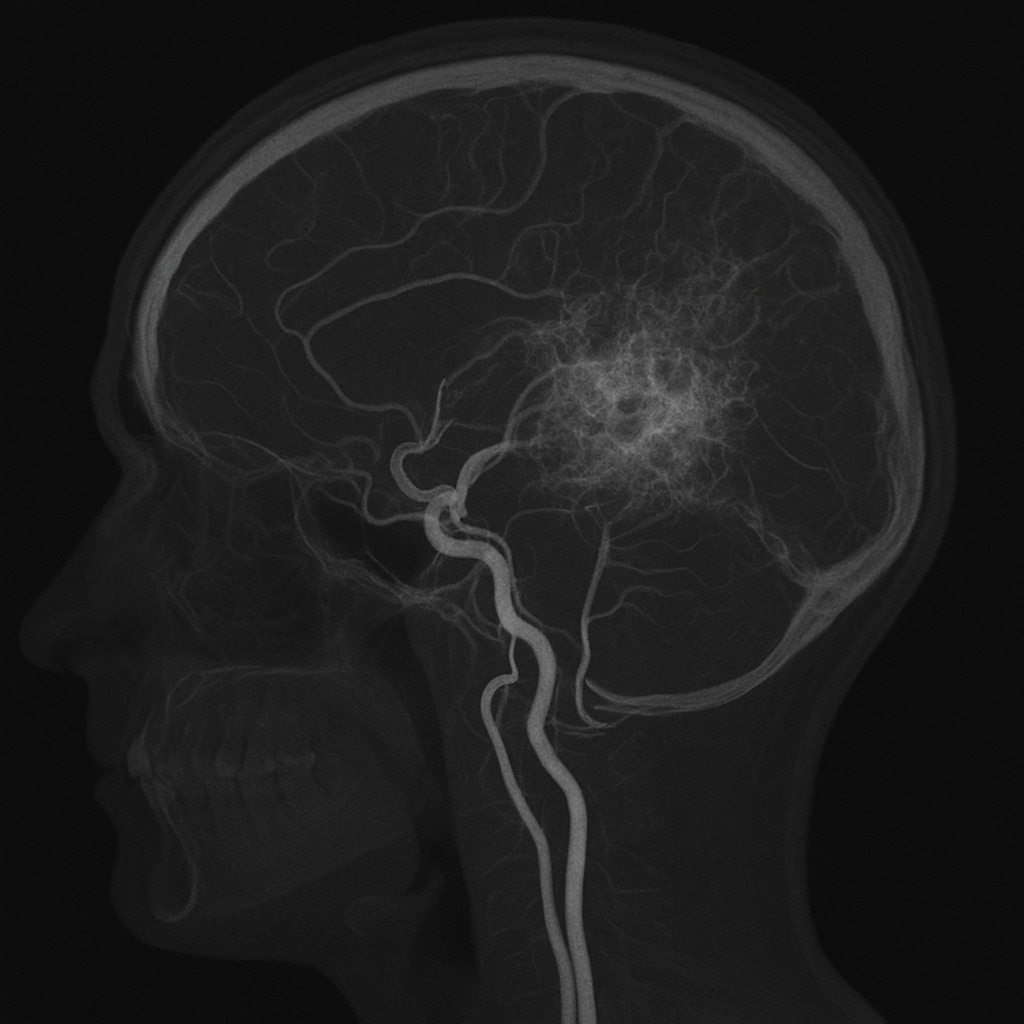

좁아진 혈류를 보완하기 위해 주변에 가늘고 새로운 혈관들이 생기는데 이 모습이 마치 연기처럼 안개 낀 것처럼 보여 ‘모야모야’라는 이름이 붙여졌다.

주요한 변화는 내경동맥의 말단 부위, 전대뇌동맥 및 중대뇌동맥의 기시부에서 일어난다.

2. 뇌혈관 조영술

정확한 진단을 위해 시행되며, ‘모야모야혈관’이 선명히 보임

진단의 핵심은 혈관이 얼마나 막혀 있는지, 그리고 보상적으로 생성된 혈관 구조가 ‘모야모야형’인지 확인하는 것이다.